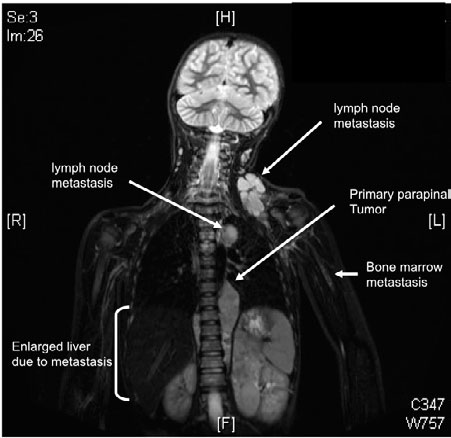

Magnetresonanzaufnahme eines Neuroblastom-Patienten, bei dem sich bereits Metastasen in den Lymphknoten und im Knochenmark gebildet haben. Außerdem kann man den primären Tumor neben der Wirbelsäule erkennen sowie eine wegen der Metastasen vergrößerte Leber.

Uni-Kinderklinik Heidelberg, Prof. Dr. Olaf Witt